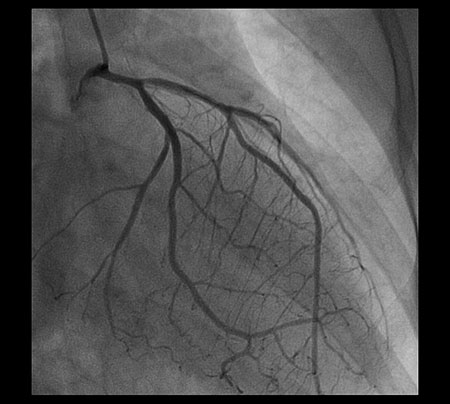

来院時の心電図ではv1 〜 v5 までST 低下所 見を示し、心筋虚血が疑われた(図3)。同日緊 急CAG を施行したところLMT からLAD にか けて狭窄を認めたが(図4)、硝酸イソソルビドの冠動脈注入で狭窄は拡張し改善した(図5)。

図4

図4 :緊急CAG 所見を示す。誘発試験は行っていないが、自然発作でLMT は50 〜 75 %程度の狭窄、LAD just proximal が90 %の狭窄を示している。

図5

図5 : ISDN 冠動脈注入後のCAG。LMT からLAD は拡張しており、器質的な狭窄はない。